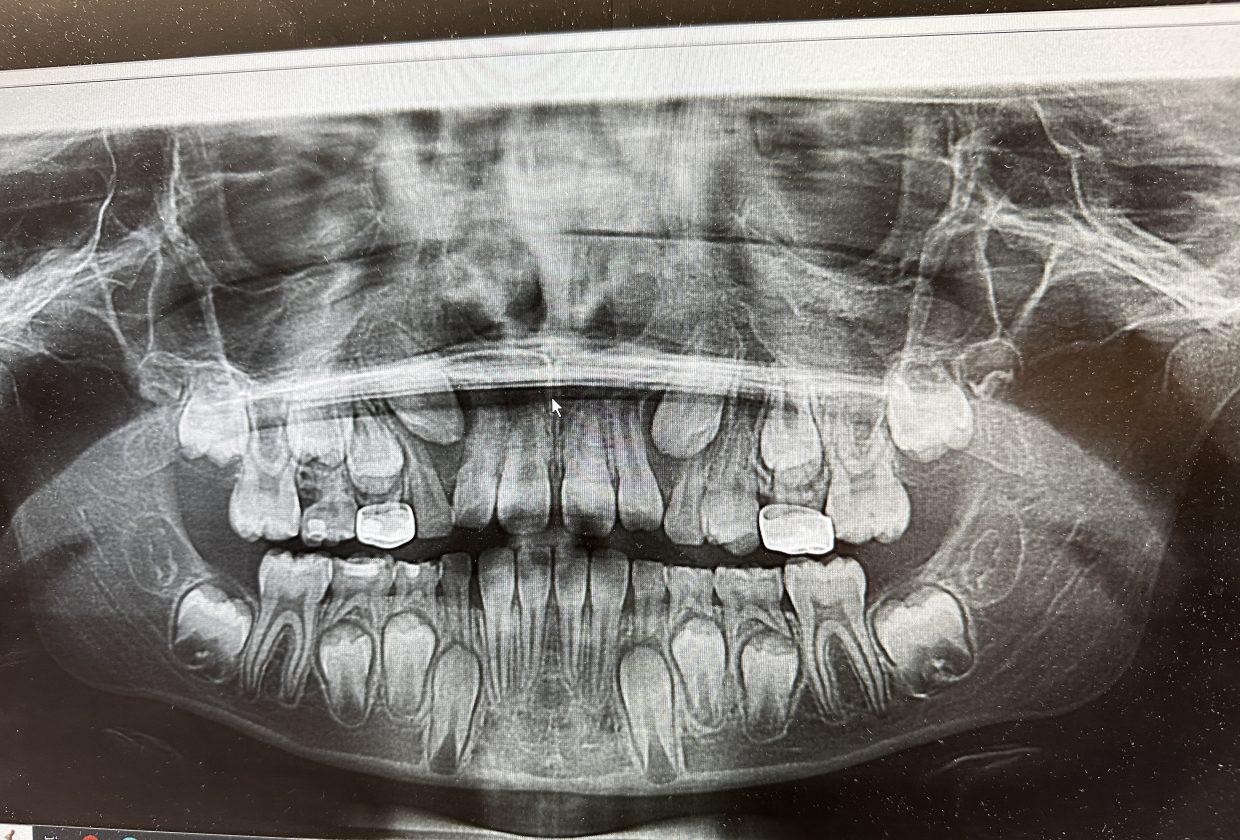

The dentist did say that I’m going to need to see an orthodontist soon, especially because of that #6 tooth coming in weird, but that’s for another day!